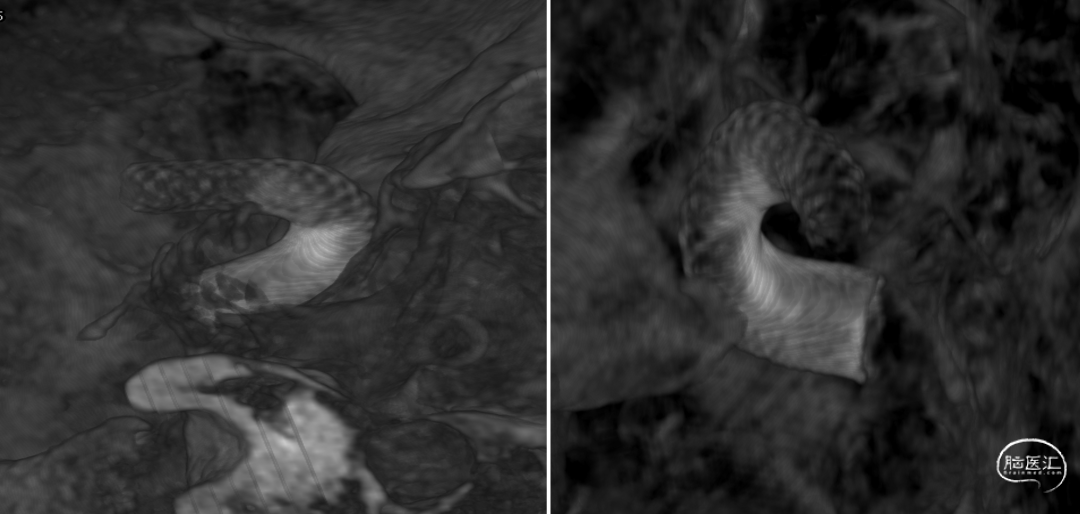

左颈内动脉3D重建图像(4.6mm*4.9mm)

半年后全脑血管造影复查-3D重建(2023-01-18)

半年后全脑血管造影复查-3D重建及透视(2023-01-18)